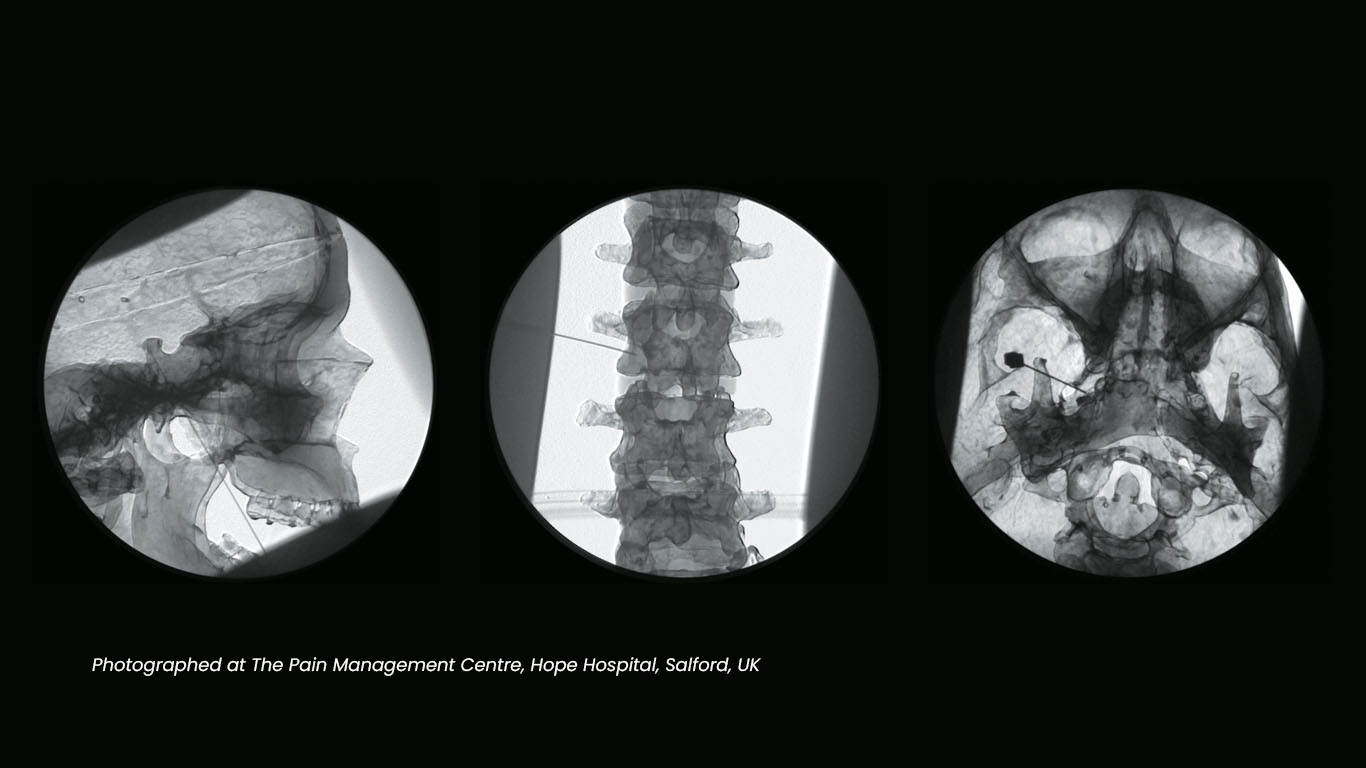

Procedure of the Week Lumbar Sympathetic Block Pain Management Block Pain Relief Nerve blocks ease pain by offering immediate relief. Nerve blocks are an effective way to prevent, reduce, or manage pain. They disrupt pain signaling around the body. Discuss these with your healthcare provider. Unlike peripheral nerve blocks, epidurals offer temporary relief and may require multiple treatments. A nerve block may be used to treat some kinds of chronic pain. Often. Block Pain Relief.